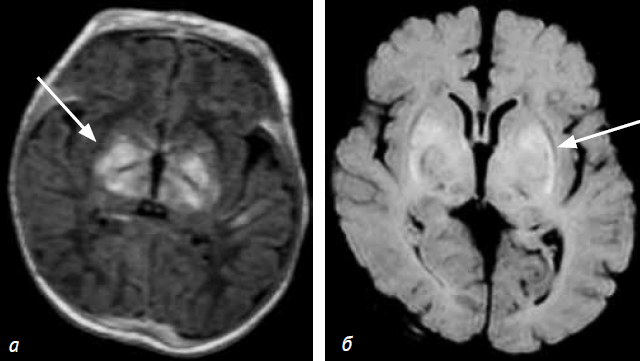

МР-изменения (на 16-е сутки жизни) включали патологическое усиление МР-сигнала на Т1 ВИ и Flair от бледного шара, вентролатеральных ядер зрительных бугров, лентиформных ядер с обеих сторон (рис. 2). Усиление МР-сигнала на Т1 ВИ отмечалось также от гиппокампальной и парагиппокампальной извилин, по ходу КСТ. Значения КФА в симметричных зонах прохождения кортикоспинального тракта представлены в таблице № 1. Контрольная МРТ головного мозга выполнена в возрасте 6 недель. Сохраняется усиление МР-сигнала на Т1 ВИ и Flair ВИ от бледного шара и вентролатеральных ядер зрительных бугров, лентиформных ядер, гиппокампальной и парагиппокампальной извилин, по ходу кортикоспинального тракта. С обеих сторон на фоне вышеописанных изменений прослеживаются сформировавшиеся ликворные кисты, расположенные у наружного края передних отделов внутренней капсулы (рис. 3).

Рис. 2. Пациент C. (16 дней), Т1 ВИ (а, б) и Flair (б). Определяются патологические гиперинтенсивные МР-сигналы от вентролатеральных ядер зрительных бугров (а), бледного шара (б)

Рис. 3. Пациент C. МРТ головного мозга в возрасте 6 недель (контрольная группа): Т1 ВИ (а) и Flair (б). Определяются гиперинтенсивные МР-сигналы от вентролатеральных ядер зрительного бугра и лентиформных ядер (а). Прослеживаются сформировавшиеся кисты, расположенные в области скорлупы с обеих сторон (б)